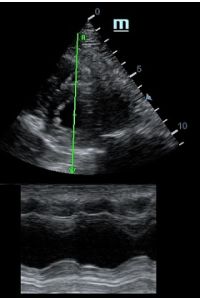

Но как же провести стандартные измерения в М-режиме, если мы его не использовали? На помощь приходит функция Free Xros M – анатомический М-режим. Имея записанную в память прибора видео петлю, мы можем провести линию М-режима в любом месте, при этом корректируя изначально не оптимальный угол.

Оценка кооптации нижней полой вены ещё никогда не была такой простой и точной, никаких лишних деталей, просто устанавливаем клипер по анэхогенному участку.